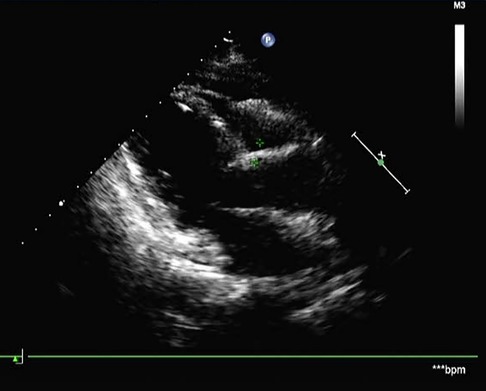

A 68-year-old female was admitted to the hospital with a chief complaint of paroxysmal chest tightness, shortness of breath, and palpitation for over a month. The patient had no history of hypertension or diabetes mellitus and other comorbidities. Preoperative echocardiography showed an intracardiac mass with medium-level echogenicity attached to the upper part of the interatrial septum in the left atrium, with a wide base, regular shape, and fixed position (Figure 1A). The coronary CTA showed a spherical lesion of equal density in the left atrium, closely related to the upper part of the interatrial septum, with right coronary artery blood supply (Figure 1B). Cardiac magnetic resonance imaging (MRI) depicted a spherical lesion with mixed isointense T1 and hyperintense T2 signal in the left atrium, with a clear edge and a size of approximately 2.5 cm × 2.6 cm × 2.7 cm. Late gadolinium-enhanced (LGE) imaging demonstrated patchy and uneven delayed enhancement in the left atrial mass (Figure 1C). Coronary angiography prior to surgery revealed the blood perfusion from the distal right coronary artery to the left atrial mass (Figure 2).

FIGURE 1

www.frontiersin.org

Figure 1. Preoperative echocardiography, coronary CTA, and cardiac MRI. (A) Echocardiography showed a medium echogenic mass attached to the upper part of the interatrial septum in the left atrium, with a wide base, regular shape, and fixed position. (B) Coronary CTA demonstrated a spherical lesion in the left atrium with right coronary artery blood supply. (C) LGE imaging depicted a spherical mass having a size of approximately 2.5 cm × 2.6 cm × 2.7 cm in the left atrium, with an abnormal signal showing a clear edge and patchy and uneven delayed enhancement.

Postoperative histopathology demonstrated that the lesion tissue was a left atrial myxoma, presenting with partial cavernous hemangioma showing vascular dilation and congestion (Figure 3B). Postoperative echocardiography did not detect any residual tumor tissue, and cardiac chamber structure and function were normal (Figure 4).

FIGURE 4

Figure 4. Postoperative echocardiography showed no residual tumor tissue and a normal cardiac chamber structure.